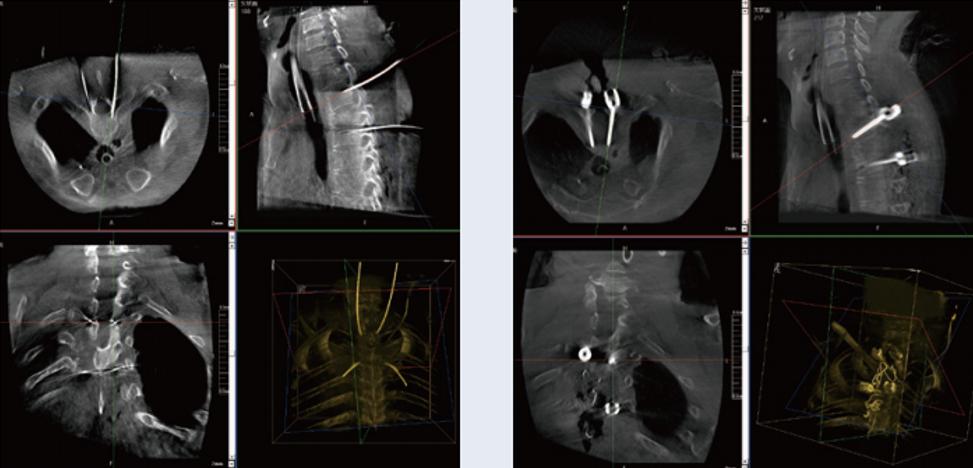

螺釘規劃后的圖像

三維C臂與骨科導航機器人配合應用(助力骨科手術更準確)

植入螺釘后的圖像

術中三維C臂與骨科導航機器人配合應用,實現準確定位,確保了手術安全、高效完成。術后二維、三維影像顯示手術效果良好,達到預期目的。